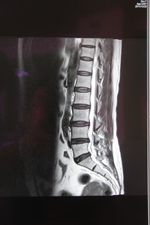

近期,我院今年新购的德国西门子MAGNETOM Avanto I-Class全身磁共振成像系统经过安装调适后正式投入使用。该系统为目前世界上最先进的1.5T磁共振,可以进行全身各部位的高质量扫描。该系统最突出的优势是:成像速度快、图像质量高,扫描覆盖范围大、扫描噪音小。患者在得到最快捷、最准确诊断的同时,还能享受到最舒适安静的检查。

该系统尤其在肿瘤诊断方面具有其突出的优势:一、个是分辨率好;二、反映的特性比较多,有利于临床把握肿瘤的诊断。三、它可以一次性的完成全身的核磁检查,第一次真正做到了高分辨的全身成像。可以很好的评估肿瘤的转移扩散程度,也通过全身的弥散成像使我们了解局部的淋巴结和全身的淋巴结,从其它医院完成的大量的病例来看,Avanto在全身肿瘤的筛查、评估方面准确性非常高。这为我院的肿瘤影像诊断提供了一个新的,有力的武器,为正常人进行磁共振全身疾病筛查带来福音。可真正做到对疾病早发现、早诊断、早治疗,使患者得到优质的医疗服务。